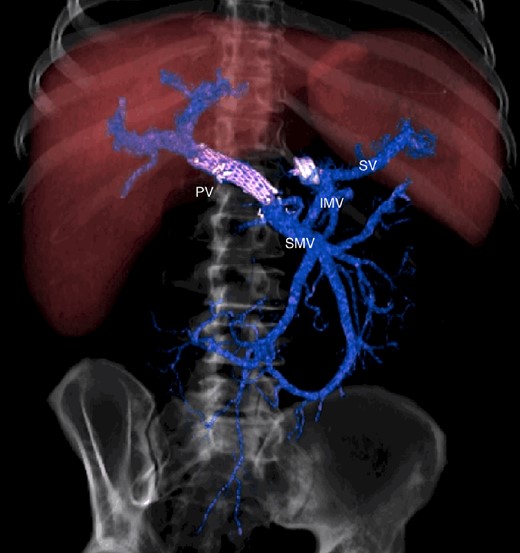

The abdominal exploration was difficult due to significant inflammatory adhesions, which can be attributed to the presence of a pancreatic fistula and the delay of relaparotomy. There was no bleeding observed within the abdominal cavity, and no bleeding was seen from the multitubular drain during the exploration. We hypothesized that the bleeding was of venous origin caused by drain-induced recurrent erosion of peripancreatic vessels, resulting in intermittent bleeding, and that removing drains could help in attaining venous hemostasis. As a result, it was decided to remove the drains. However, this resulted in a significant hemorrhage via the drain orifice. Due to failure to identify the exact origin of bleeding and without the possibility of completion pancreatectomy, we performed a damage control procedure by packing through the drain orifice. This successfully stopped the bleeding. A postoperative CT scan located the packing sponges anterior to the spleno-mesenteric confluence (SMC) (Fig. 2). A percutaneous transhepatic portography showed an irregular aspect of the SMC, without thrombi or contrast extravasation (Fig. 3). After consulting with the interventional radiology team, we placed a cover stent (Fluency™ Bard, Murray Hill, USA) in the SMC (Fig. 4). Two days later, we removed the packs, and a massive hemorrhage recurred, necessitating a new packing. The stent was not seen on a subsequent CT scan. We then performed an endovascular procedure to exclude the segment of the irregular SMC. An Amplatzer™ vascular plug (Abbott Vascular, Santa Clara, USA) was placed in the splenic vein, extending distally to just surpass the inferior mesenteric vein (IMV) insertion (Fig. 5). A cover stent was subsequently deployed in the portal vein, extending distally to the superior mesenteric vein. This allowed for the exclusion of the splenic vein segment that lies between the inferior mesenteric vein insertion point and the spleno-mesenteric confluence (Fig. 5). The packing sponges were removed 10 days later without bleeding recurrence, and the patient finally showed clinical improvement. After 3 years, the stent was visible and permeable on a follow-up CT scan. The scan showed development of venous collaterals, which drain the distal splenic vein and inferior mesenteric vein through the lesser omentum (Fig. 6).

CT scan after other interventional radiology with plug in the splenic vein and cover stent in the superior mesenteric vein. PV portal vein, SMV superior mesenteric vein, SV splenic vein, IMV inferior mesenteric vein.